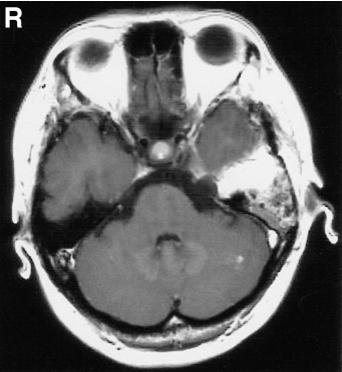

图1(上排)伽玛刀放射治疗(GKR)前轴位和冠状位t1加权磁共振(MR)增强图显示左侧中窝和左侧后窝肿瘤,外观坚实,强化均匀。(下行)GKR术后18个月,轴位和矢状位t1加权钆成像显示肿瘤包含多个囊肿,并明显压迫脑干,囊肿后部周围有假囊,与后颅窝硬脑膜相连。

入院时,MR示左侧中后颅窝一哑铃状肿瘤,t1低强度,t2高强度。肿块内有多个囊肿,实性部分增强均匀。肿瘤后部形成囊肿,囊部强化,与后颅窝硬脑膜连续,明显压迫脑干,肿瘤大小为4.5×2.5×2.5 cm(图1下排)。